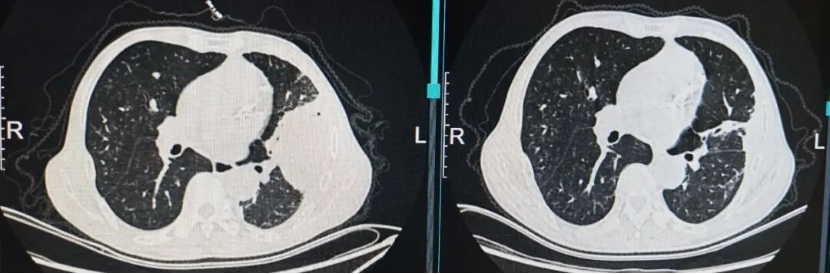

治疗:患者同意参加由中日友好医院牵头,上海市肺科医院为参与单位的临床研究《两性霉素B脂质体 (AmBisome®)联合艾沙康唑与AmBisome®单药治疗肺毛霉菌病的疗效和安全性比较的多中心、前瞻性、开放、随机对照研究》,通过随机化入组了两性霉素B脂质体单药治疗组。2026年2月13日起予两性霉素B脂质体5mg/kg/d静滴治疗,2月16日复查肾功能示血肌酐111.6umol/L升高,考虑肾功能损伤,2月17日起两性霉素B脂质体减量至3mg/kg/d静滴治疗,同时予水化、保肾等治疗。2月19日复查肾功能血肌酐98.7umol/L,较前有下降好转,继续两性霉素B脂质体3mg/kg/d静滴治疗,监测血常规、肝肾功能电解质。2月23日复查胸片示左肺实变影较前有所吸收好转(图片3)。两性霉素B脂质体静滴疗程满28天,2026年3月11日复查胸部CT示左肺实变影基本完全吸收好转(图片4)。2026年3月12日予出院续贯口服艾沙康唑治疗。在药物治疗的同时,营养支持也很重要,患者入院时血生化示白蛋白32.1g/L,前白蛋白120.3mg/L,遵医嘱每日食用3-4个鸡蛋补充蛋白质,出院时白蛋白升至43.4g/L,前白蛋白318.5mg/L(图片5)。

图片4:两性霉素B脂质体静滴治疗28天胸部CT对比左肺实变影基本完全吸收好转。